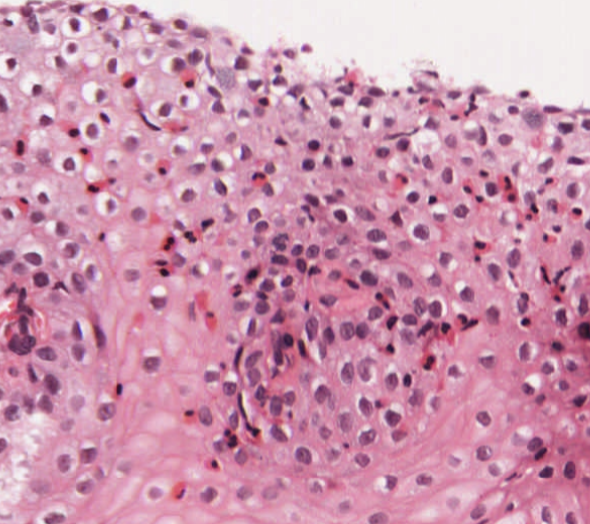

#caseoftheweek 🔬🔬🔬🔬What is causing this lesion from the skin of a 50 year old woman? S100 and PAS-D positive #dermpath #pathtwitter #pathX Full slide here: virtualpathology.leeds.ac.uk/slides/library…